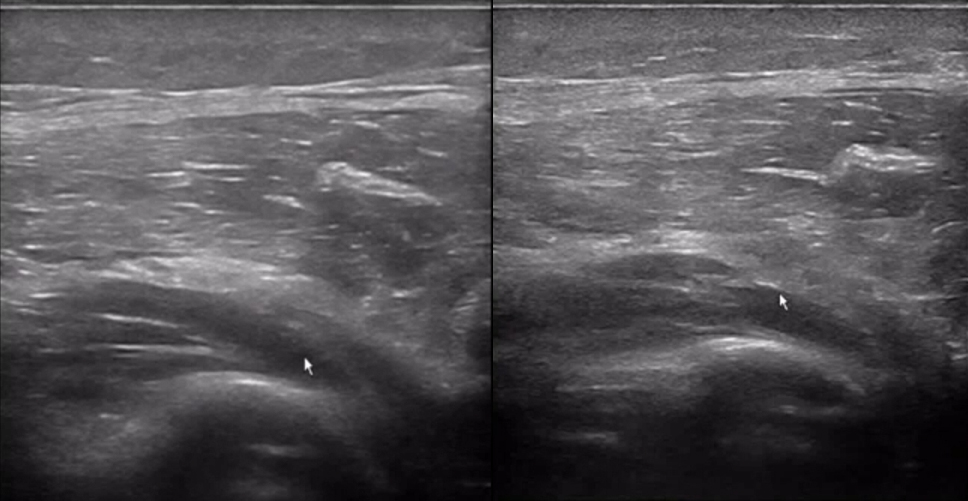

A traumatic injury to the forearm caused by a dropped drill led to impaired extension of the thumb and index finger.

The handheld ultrasound machine showed significant swelling and thickening of the deep branch of the radial nerve, with disrupted and non-continuous nerve structures.

Here, the portability and precision of the ultrasound machine were essential for assessing the extent of nerve damage and guiding further management.